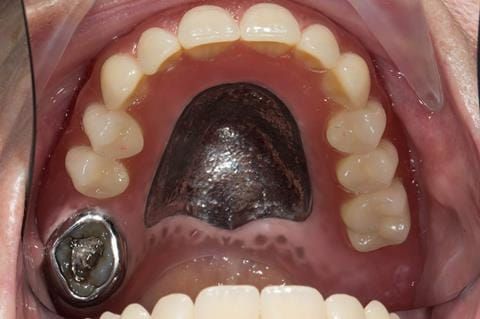

- Poorly fitting cobalt chromium based maxillary partial denture, which has been added to. This exhibited poor retention, stability and tissue fit (support). Unable to wear a new acrylic based denture.

- UR7 - occlusal amalgam. 10- 20% alveolar bone loss. Healthy periodontium with reduced attachment level. No mobility.

- Eight mandibular anterior teeth worn incisal edges from now extracted maxillary anterior crowns. Gingivitis - owing to inadequate oral hygiene.

- LL6 with large amalgam restoration - healthy periodontium.

- Bruxism.